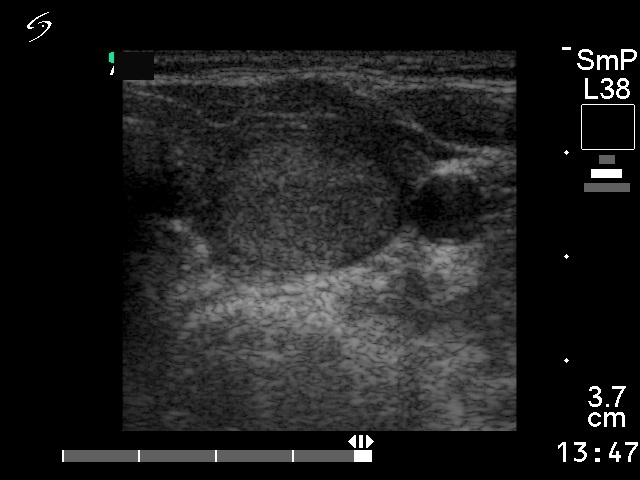

Follicular adenoma - Case 25. |

Clinical data: a 61-year-old woman with an elevated TSH-level detected on screening.

Palpation: a solitary nodule in the left lobe.

Functional state: subclinical hypothyroidism with TSH-level 5.00 mIU/L.

Ultrasonography: a solitary echonormal nodule within the moderately hypoechogenic left lobe.

Cytological report: suspicion of papillary cancer.

Suggestion: surgery.

Histopathology: microfollicular adenoma and focal lymphocytic thyroiditis.